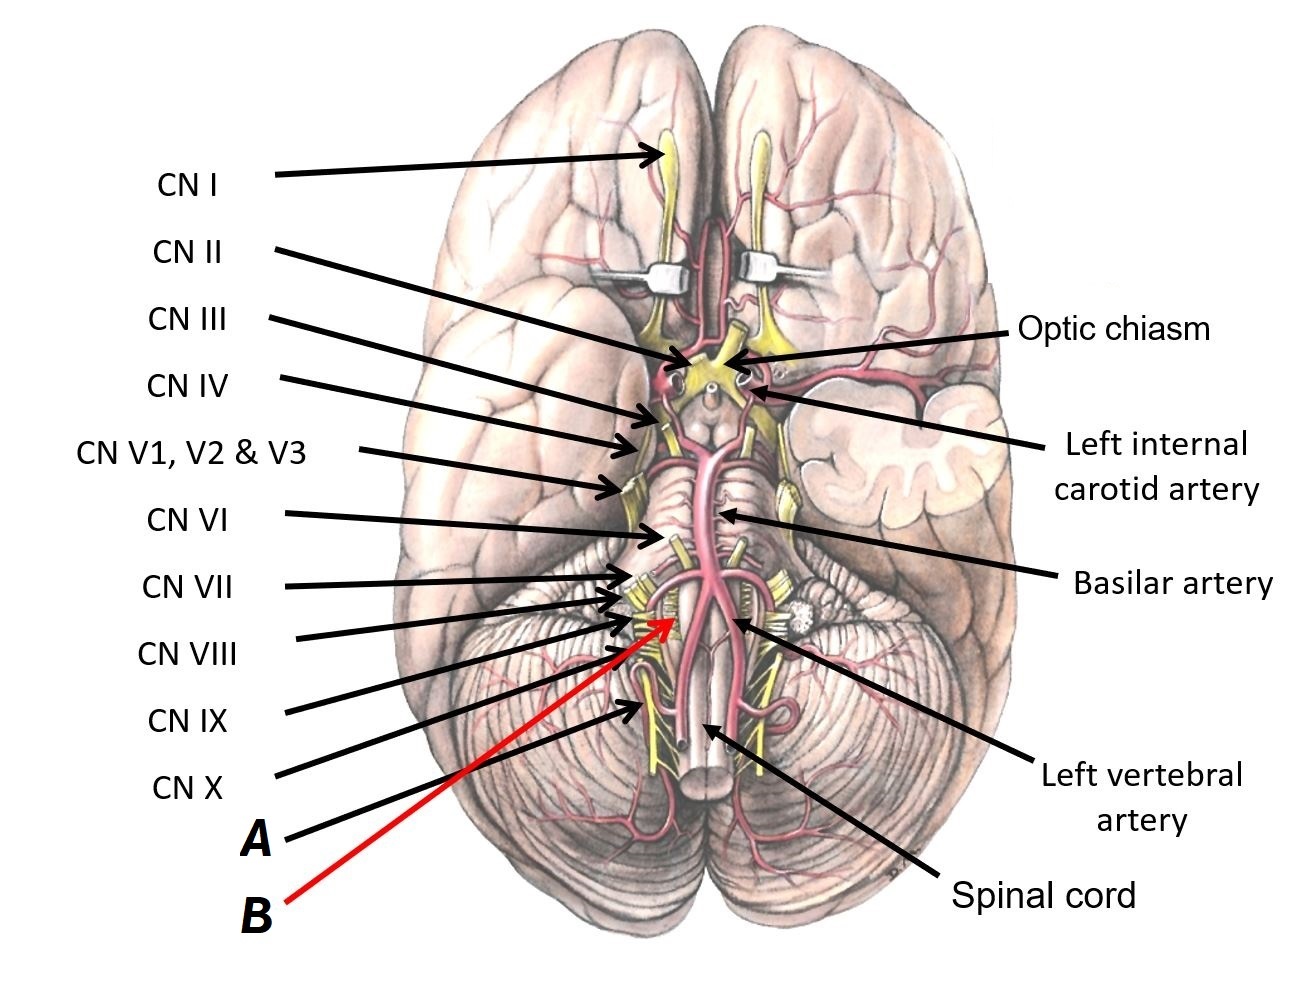

Name nerves A and B

A - CN XI (accessory nerve)

B - CN XII (hypoglossal nerve)

Name structures A to D

A - Optic chiasm

B - Left internal carotid artery

C - Basilar artery

D - Left vertebral artery